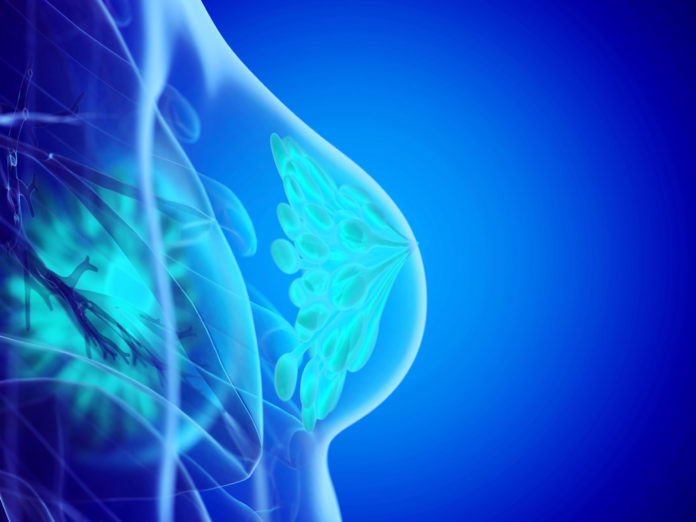

Véritable avancée pour la santé des femmes, le dépistage du cancer du sein, tel qu’il est pratiqué depuis quinze ans, pourrait encore être amélioré et préserver la vie de plus de patientes.

Le cancer du sein est le plus fréquent et le plus mortel chez les femmes : 60 000 nouveaux cas chaque année et 12 000 décès.

Il touche 1 femme sur 8 en France. 50 % des cas surviennent chez des femmes entre 50 et 69 ans ; 28 % après 70 ans. Depuis 2004,

ce cancer fait l’objet d’un dépistage organisé : tous les deux ans, les femmes de 50 à 74 ans sont invitées par courrier à pratiquer

une mammographie dans un centre de radiologie agréé de leur choix, prise en charge à 100 %.

Les spécialistes estiment que cet examen régulier permet d’éviter plus d’un décès sur cinq.

« Chaque année, plus de 10 000 cancers agressifs peuvent être ainsi soignés plus tôt », selon l’Institut national du cancer.

Des examens adaptés à chaque femme

Depuis quelques années, le dépistage systématique est parfois remis en question, en particulier à cause du risque de sur-diagnostic et donc de sur-traitement, des faux-positifs, de l’exposition répétée à des rayonnements ionisants… Aussi commence-t-on à envisager un dépistage personnalisé, adapté au risque de chaque femme. Il se calculerait à partir de l’âge, des antécédents médicaux personnels et familiaux, de la densité des seins. Le génotype, qui analyse les variations de l’Adn modifiant l’expression des gènes protecteurs vis-à-vis du cancer du sein,

et de ceux qui en revanche, en augmentent les risques, serait aussi pris en compte.

Ainsi, si la femme a un risque élevé de développer la maladie, elle ferait une mammographie tous les ans et si le risque est faible, tous les quatre ans.